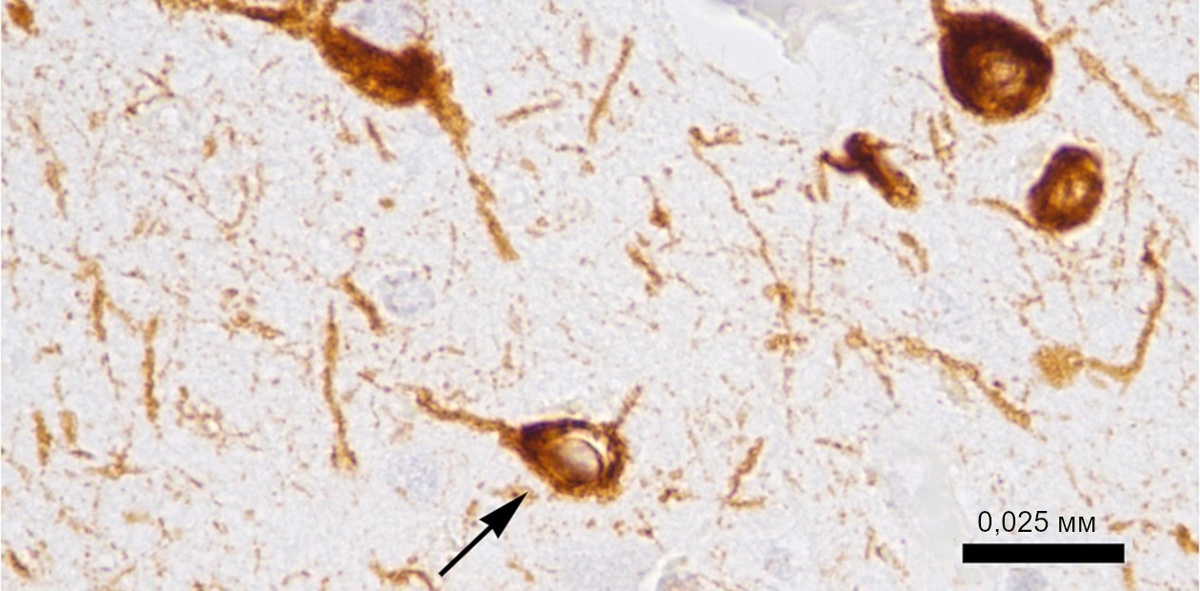

Нейроны (показано стрелкой) пациента, умершего от болезни Альцгеймера. Тау-белок окрашен с помощью иммуногистохимических препаратов в коричневый цвет. © CC BY-SA 4.0/Tulemo

Новый препарат ALPHA-003 предназначен для лечения группы заболеваний, известных как тауопатии – по названию тау-белка, аномальная агрегация которого в нейронах, как известно, сопровождается формированием нейрофибриллярных клубочков, которые откладываются в нервной ткани, нарушая работу мозга. Но не все знают, что для мозга вредно не только присутствие аномального тау-белка, но и недостаток «здорового».

Нормальный тау-белок необходим для работы микротрубочек – одного из ключевых структурных компонентов цитоскелета, совокупности белковых структур, составляющих «опорно-двигательный аппарат» клетки. Микротрубочки работают как «рельсы» для транспортировки по клетке различных молекул, участвуют в поддержании ее формы и правильного расположения клеточных органоидов. А тау-белок укрепляет их, обеспечивая успешную динамическую перестройку. При изменениях пространственной конфигурации этого белка микротрубочки дестабилизируются, что приводит к нарушениям связей между органеллами и передачи нервного импульса.